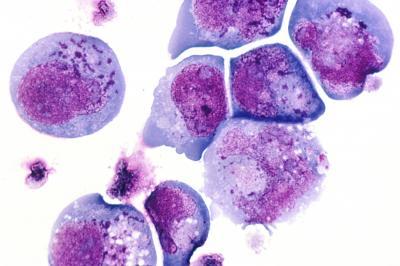

Human herpesvirus 6, pictured above, is just one of numerous viruses found living in and on the bodies of healthy humans. The virus commonly causes illness in young children but is found in the mouths of some healthy young adults, where its presence indicates an active viral infection despite a lack of symptoms.

(Photo Credit:

Wikimedia Commons (Public Domain))